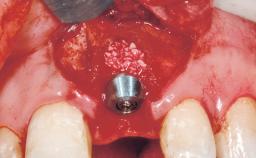

Type of Implants One-Piece

Bone Augmentation Horizontal|Staged

Augmentation Materials Xenogenous|Membrane

Soft Tissue Grafting Simultaneous

Bone Volume Deficient horizontally, requiring prior grafting